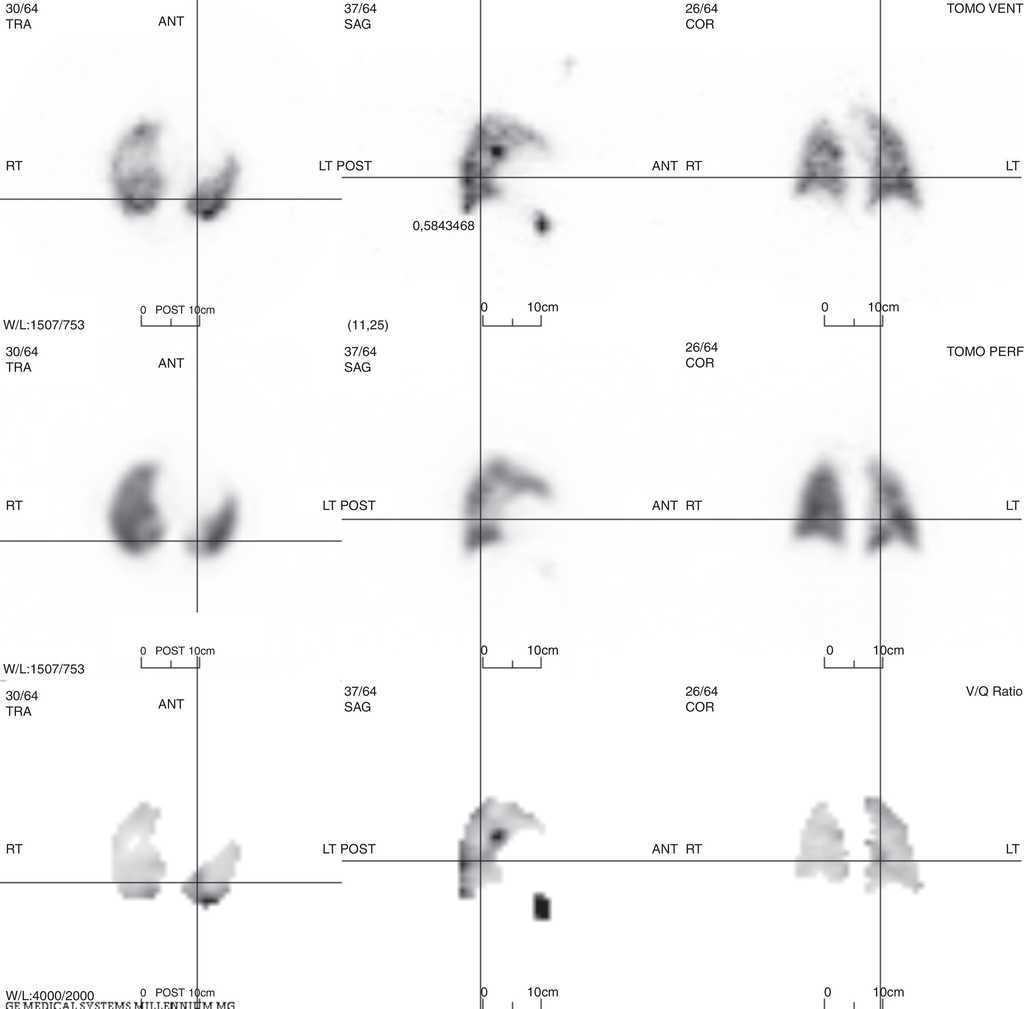

Figure 3, Figure 4, Figure 5 illustrate V/QS-SPECT larger sensitivity to detect perfusion defects. These examples demonstrate how, in one patient, V/QS-planar fails to correctly identify important perfusion defects, therefore failing to diagnose PTE, while V/QS-SPECT accurately documents them

Figure 4. V/QS-SPECT study, same patient as before; it is clear that there is a perfusion defect in the superior segment of the left lung's lower lobe (cross-hairs) fulfilling PTE diagnostic criteria.

Figure 5. V/QS-SPECT study, same patient as before; another perfusion defect fulfilling PTE diagnostic criteria, this time in the lateral basal segment of the left lung's lower lobe (cross-hairs).